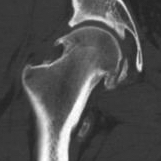

CT

Cam impingement